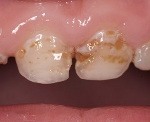

Стадия поверхностного кариеса (16. 24 месяцев) - характеризуется образованием дефекта в пределах зубной эмали и обнажением дентина. Поверхностный кариес поражает не только пришеечные области резцов и клыков, но и проксимальные и окклюзионные поверхности верхних моляров. Кариозные очаги имеют светло-желтый или коричневатый цвет, возникает гиперестезия зубов. Поверхностный бутылочный кариес требует препарирования и пломбирования полости.